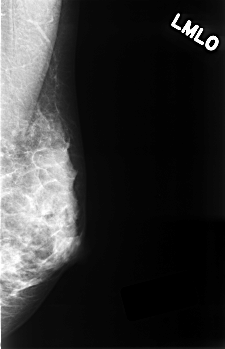

| ics_version 1.0 filename C-0336-1 DATE_OF_STUDY 22 3 1996 PATIENT_AGE 35 FILM FILM_TYPE REGULAR DENSITY 3 DATE_DIGITIZED 12 10 1998 DIGITIZER LUMISYS LASER SEQUENCE LEFT_CC LINES 4448 PIXELS_PER_LINE 2912 BITS_PER_PIXEL 12 RESOLUTION 50 NON_OVERLAY LEFT_MLO LINES 4528 PIXELS_PER_LINE 2920 BITS_PER_PIXEL 12 RESOLUTION 50 NON_OVERLAY RIGHT_CC LINES 4488 PIXELS_PER_LINE 2888 BITS_PER_PIXEL 12 RESOLUTION 50 OVERLAY RIGHT_MLO LINES 4528 PIXELS_PER_LINE 2912 BITS_PER_PIXEL 12 RESOLUTION 50 OVERLAY |

| FILE: C_0336_1.RIGHT_MLO.OVERLAY TOTAL_ABNORMALITIES 1 ABNORMALITY 1 LESION_TYPE MASS SHAPE OVAL MARGINS CIRCUMSCRIBED ASSESSMENT 4 SUBTLETY 5 PATHOLOGY BENIGN TOTAL_OUTLINES 1 BOUNDARY |